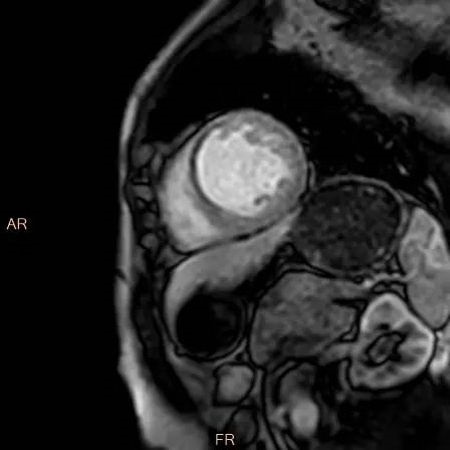

医生利用心脏磁共振检查观察心脏各组织情况,也可用于检查患者是否罹患以下疾病:1.先天性心脏病;2.非缺血性心脏病;3.缺血性心脏病;4.手术或外伤评估;5.瓣膜疾病;6.心包疾病;7.肿物。

1.心脏的解剖结构问题,比如:异常连接、分流、狭窄、外科手术前评估及随访,房间隔缺损、室间隔缺损、粘液瘤、血栓、心肌肥厚(流出道是否梗阻)以及增大或缩小的心腔等。

8.占位。比如:肿物范围、性质等。

1.借助心脏电影,完成心功能分析。

4.非缺血性心肌病的评估,如肥厚性心肌病、扩张性心肌病、限制性心肌病等,心肌呈现不同程度条状、斑片状、斑点状的延迟强化。